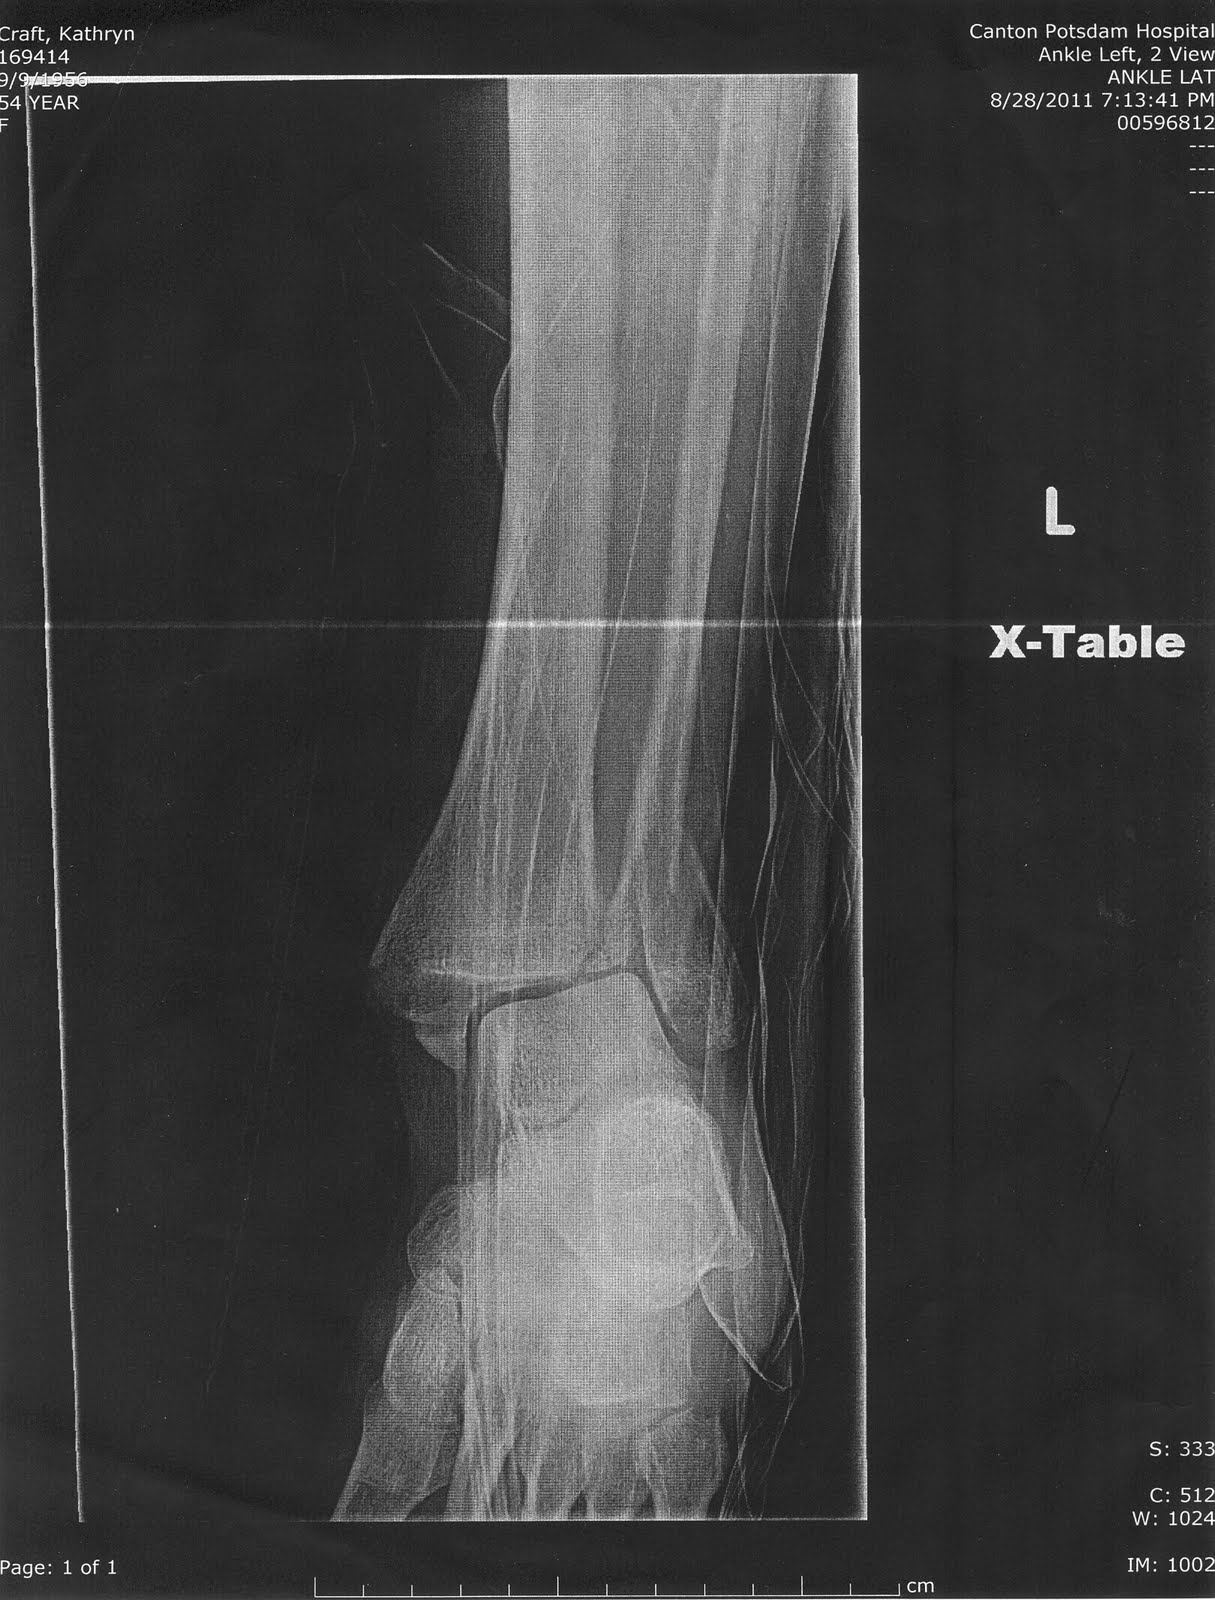

Ankle fracture essay in 2021

Ankle fracture essay image This picture representes ankle fracture essay.

The diagnosis of letter a fracture in the wrist or ankle joint is made from 2 standard photography views taken atomic number 85 right angles to each other. As broadening of the articulatio talocruralis mortise by 1 mm decreases the contact area of the tibiotalar cooperative by 42%, this could lead to instability and thu early osteoarthritis of the tibiotalar common.